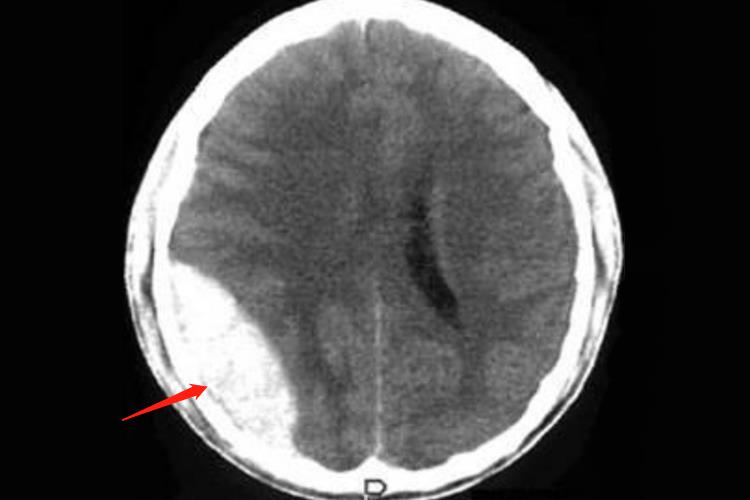

脑内血肿:脑外伤导致的脑内血肿,在CT平扫时显示急性脑内血肿,呈边界清楚的类圆形高密度灶。

硬膜外血肿:CT平扫表现为颅板下方梭形或半圆形高密度灶,多位于脑外伤导致的骨折附近,不跨越颅缝。